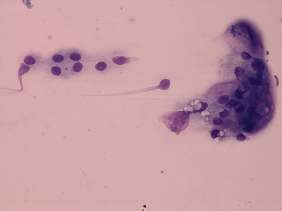

Cytology was performed from the discrete lesion in the left lobe and resulted in Hashimoto's thyroiditis.

Histopathology disclosed Hashimoto's thyroiditis without any nodule.